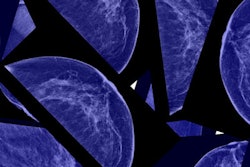

This week's top story was undoubtedly the turmoil within the antimammography-screening movement, as two of its most powerful figures left high-profile positions.

Dr. Peter Gøtzsche was ejected from the governing board of the Cochrane (formerly the Cochrane Collaboration), setting off a civil war between proponents of evidence-based medicine within the Cochrane organization and its individual centers. At almost the same time, Dr. H. Gilbert Welch resigned from Dartmouth College over allegations of plagiarism in a 2016 paper on overdiagnosis and breast screening. Our article on the developments was the top story of the week -- catch up by clicking here.

Supporters of breast screening can be excused if they are experiencing a bit of schadenfreude. Both Welch and Gøtzsche -- especially Gøtzsche -- have been thorns in their sides for years. Of the eight large randomized controlled trials on screening mammography, Gøtzsche excoriated the statistical methods used in the six that supported population-based breast screening, while upholding as gospel the two that found mammography to have no effect. He even wrote a book published in 2012, Mammography Screening: Truth, Lies and Controversy, that purported to expose breast screening as a "scandal of monstrous proportions."

While not as extreme, Welch consistently tried to poke holes in mammography's aura with a series of papers that focused on the alleged "harms" of breast screening, such as overdiagnosis and false positives. Welch's work alleged that nearly one-third of breast cancers detected by mammography screening were simply cases of overdiagnosis, and he and others proposed that the well-documented decline in breast cancer mortality was entirely due to better treatment, not screening.